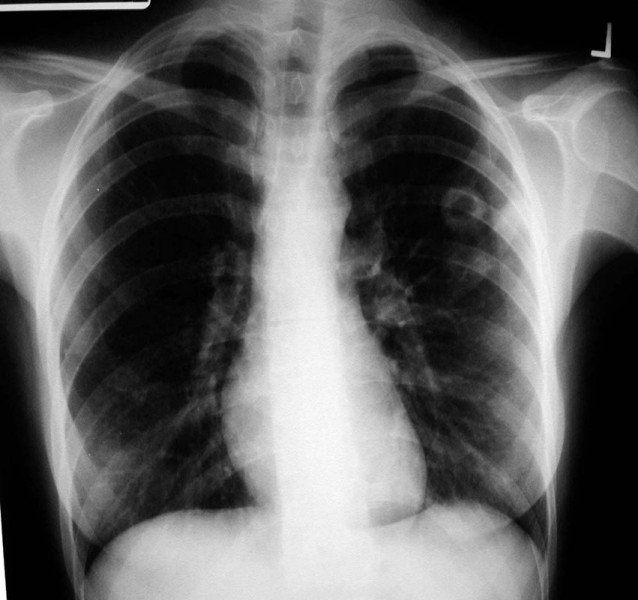

Ziua Mondială de Luptă împotriva tuberculozei, marcată la Brăila

În perioada 24 martie-10 aprilie se va desfăşura campania cu ocazia Zilei Mondiale de Lupta Împotriva Tuberculozei. La nivelul Direcţiei de Sănătate Publică (DSP) Brăila, personalul de specialitate al Compartimentului de evaluare şi promovare a sănătăţii va avea întâlniri de lucru cu cadre medicale din Spitalul de Pneumoftiziologie, în calitate de parteneri din cadrul campaniei, şi va distribui pliante şi afişe specifice temei, în spitale, cabinetele medicilor de familie şi în policlinici. De asemenea, reprezentanţii direcţiei vor informa populaţia ţintă cu privire la TBC, în cadrul unor discuţii interactive cu pacienţii, pentru conştientizarea necesităţii şi importanţei tratamentului corect în TBC, discuţii cu aparţinătorii privind importanţa urmăririi aplicării tratamentului şi îngrijirii corecte a bolnavului cu TBC, precum şi prin intermediul unor postări pe pagina web a DSP.

În judeţul Brăila, incidenţa cazurilor de TBC este în scădere în ultimii ani. Astfel, în 2013 s-au înregistrat 244 cazuri noi de TBC (5 la grupa de vârsta 0-14 ani şi 239 la grupa de vârstă peste 15 ani) şi 51 cazuri de bolnavi readmişi în evidenţe. Din total, 136 cazuri noi au fost înregistrate în mediul urban şi 108 cazuri noi în mediul rural. Dintre bolnavii readmişi, 31 au provenit din mediul urban şi 20 din mediul rural. Comparativ, în anul 2012 s-au înregistrat 256 cazuri noi de TBC (12 la grupa de vârsta 0-14 ani şi 244 la grupa de vârstă peste 15 ani ) şi 62 cazuri de bolnavi readmişi în evidenţe.

România, primul loc în Europa la tuberculoză

Conform Centrului European pentru Prevenirea şi Controlul Bolilor (ECDC), România continuă să ocupe primul loc din Europa, având cele mai multe cazuri de tuberculoză: peste 34.000, în 2013, dintre care 1.500 cazuri de tuberculoză multidrog-rezistentă. Aproximativ 1.200 bolnavi mor anual. În România, tuberculoza constituie una din problemele prioritare de sănătate publică, iar Strategia Naţională de Control al Tuberculozei are la bază direcţiile şi coordonatele stabilite de către Planul Global OMS de stopare a Tuberculozei până în 2015 şi după această dată.

În prezent, în lume există 8 milioane de cazuri de tuberculoză simptomatică, iar 3 milioane de decese se înregistrează în fiecare an. Astfel, TBC este a doua cauză infecţioasă de deces din lume, doar SIDA facând mai multe victime. Se estimează că o treime din populaţia lumii este infectată cu bacilul Koch, iar la circa 5-10% dintre aceştia infecţia latentă progresează într-o formă de boală activă.